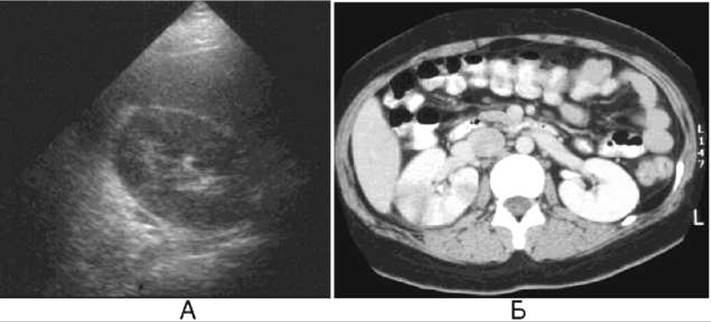

Мал. 247. Гострий правобічний пієлонефрит.

А - Ультразвукове дослідження виявляє збільшення нирки з втратою кірково-мозкової диференціації (набряк).

Б - на комп’ютерній томограмі відзначається збільшення правої нирки та смуги зниженої денситометричної щільності в паренхімі нирки.